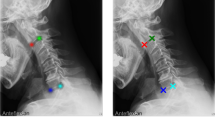

A 28-year-old woman presented after a traumatic Type I AARS without evidence of osseous injury, but MRI demonstrated evidence of unilateral alar ligament disruption. Initial conservative management with closed reduction and maintenance in a rigid cervical collar proved unsuccessful, with worsening pain and failure to maintain reduction. She subsequently underwent open reduction and surgical fixation of C1-C2, resulting in resolution of her pain and maintenance of alignment.